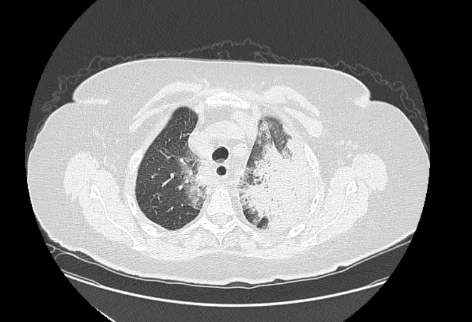

___В декабре 2024 года в пульмонологическое отделение по линии скорой медицинской помощи доставлена пациентка Б., 87 лет, с жалобами на боли в грудной клетке при дыхании, общую слабость. Заболевшей себя считает 6 дней назад, когда впервые появились боли в груди. По этому поводу принимала нестероидные противовоспалительные препараты. Обращает на себя внимание, что 4 дня назад выписана из другого стационара, где проходила лечение по поводу внебольничной двусторонней пневмонии. Госпитализирована в отделение пульмонологии с диагнозом «пневмония». На фоне стартовой терапии пациентка прошла с отрицательной динамикой. Основная причина ухудшения – пароксизм фибрилляции предсердий с развитием церебральной и сердечно-сосудистой недостаточности. В этой связи переведена в отделение анестезиологии и реанимации, где потребовалось протезирование дыхательной функции на фоне нестабильной гемодинамики. Путем объемного экстренного дообследования исключена тромбоэмболия легочной артерии. Больная погружена в медикаментозный сон, переведена на ИВЛ. Обследована, пароксизм фибрилляции купирован. Однако к этому моменту правое легкое было поражено на 100%, а в левом имелись выраженные очаги повреждения.

___Источник инфекции – бактерии, устойчивые к обычным антибиотикам. Параметры ИВЛ на момент старта лечения установлены «жесткие». Лечение в реанимации включало как поддержание медикаментозного сна и ИВЛ, так и вазопрессорную поддержку, антибактериальную, антигрибковую терапии, коррекцию водно-электролитных нарушений, профилактику острых стрессовых язв, зондовое питание, мероприятия общего ухода. Больной выполнены операции по катетеризации центральных вен, установлена трахеостома. Общий прогноз с учетом возраста, основной и сопутствующей кардиальной патологии крайне сложный.

___Вместе с тем, постепенно состояние пациентки удалось относительно стабилизировать. В течение 2х недель параметры вентиляции несколько смягчились. Однако степень повреждения была такова, что полный отказ от ИВЛ был по-прежнему невозможен.